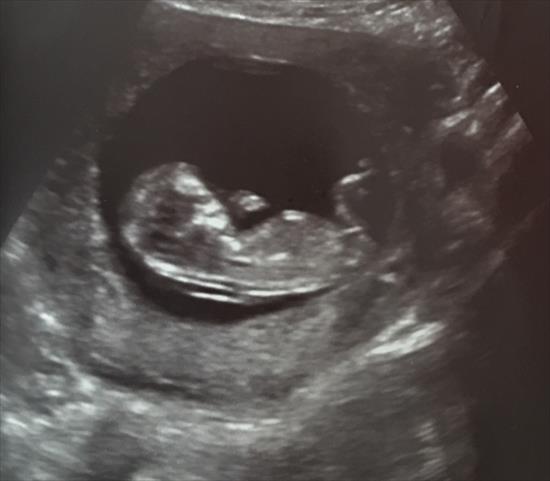

12 weeks 2 days

the nub is kinda hidden in this picture. But I was watching the nub the whole time during my scan and I saw a small ball on top of the bright white line. The ball isn’t shown in this pic though. Maybe u can see it if you zoom in extremely. I wish she would have given me better nub shots. Can u make a guess at all?